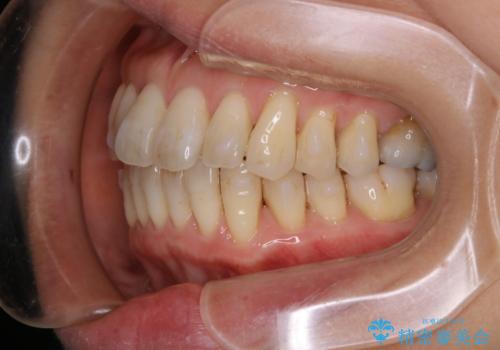

インビザラインによる非抜歯矯正を行いました。

IPRと呼ばれる、歯と歯の間を削る処置を行い、

がたつきを改善し歯を内側に入れることに成功しました。